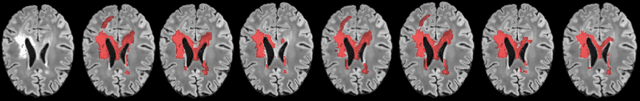

Abstract:Supervised machine learning algorithms, especially in the medical domain, are affected by considerable ambiguity in expert markings. In this study we address the case where the experts' opinion is obtained as a distribution over the possible values. We propose a soft version of the STAPLE algorithm for experts' markings fusion that can handle soft values. The algorithm was applied to obtain consensus from soft Multiple Sclerosis (MS) segmentation masks. Soft MS segmentations are constructed from manual binary delineations by including lesion surrounding voxels in the segmentation mask with a reduced confidence weight. We suggest that these voxels contain additional anatomical information about the lesion structure. The fused masks are utilized as ground truth mask to train a Fully Convolutional Neural Network (FCNN). The proposed method was evaluated on the MICCAI 2016 challenge dataset, and yields improved precision-recall tradeoff and a higher average Dice similarity coefficient.

Abstract:This paper explores the use of a soft ground-truth mask ("soft mask'') to train a Fully Convolutional Neural Network (FCNN) for segmentation of Multiple Sclerosis (MS) lesions. Detection and segmentation of MS lesions is a complex task largely due to the extreme unbalanced data, with very small number of lesion pixels that can be used for training. Utilizing the anatomical knowledge that the lesion surrounding pixels may also include some lesion level information, we suggest to increase the data set of the lesion class with neighboring pixel data - with a reduced confidence weight. A soft mask is constructed by morphological dilation of the binary segmentation mask provided by a given expert, where expert-marked voxels receive label 1 and voxels of the dilated region are assigned a soft label. In the methodology proposed, the FCNN is trained using the soft mask. On the ISBI 2015 challenge dataset, this is shown to provide a better precision-recall tradeoff and to achieve a higher average Dice similarity coefficient. We also show that by using this soft mask scheme we can improve the network segmentation performance when compared to a second independent expert.